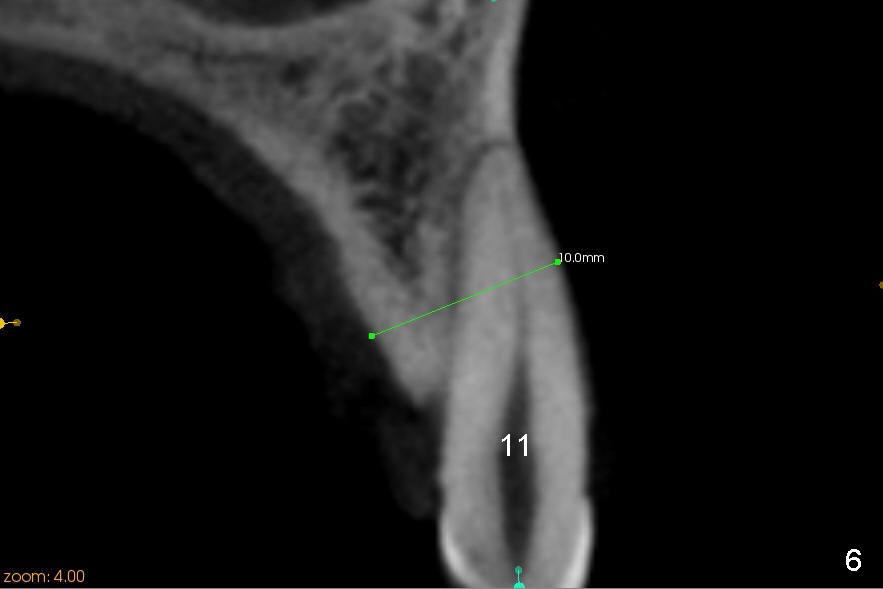

A 45-year-old lady has history of chronic periodontitis. The tooth #6 has lost several years (Fig.1). The buccolingual width decreases (Fig.2 (7mm), as compared to #11 in Fig.6 (10 mm)). Bone expansion is necessary for implantation. It should be done gently, since she is a dental phobic. First the crestal cortex is split with a surgical fissural bur (Fig.3 red line), followed by thin osteotomes (Fig.4 green line: scalpel, bone scalpels (probably until 5 or 6 mm, as indicated by Fig.1 (mesiodistal width)), bone blades (until 5.5 mm)). If the patient cannot tolerate tapping, 1.6 mm pilot drill is used at the depth of 14 mm, followed by bone expanders (probably until 2.9/3.8 using handpiece). As expanders or rounded osteotomes increases in diameter (Fig.5 green arrow), the buccal plate moves buccally (pink arrow). The bone expansion improves cosmetics as well. The implant is planned to be 4.5x14 mm, bone level. Angled abutment is expected. In contrast, immediate implant prevents buccal plate atrophy and avoids bone expansion. How is the surgery?